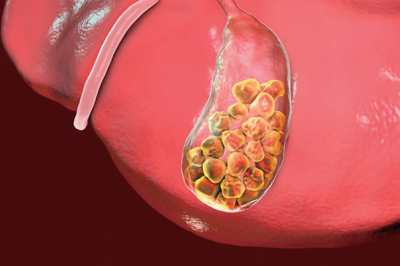

胆石病:肥胖者容易患胆石病

近年来,随着人们生活水平的提升,我国胆石病的发生率也呈上升趋势。胆石病包括发生在胆囊和胆管的结石。胆石可发生在胆管系统的任何部位,胆囊内的结石为胆囊结石,左右肝管汇合部位以下的包括肝总管结石和胆总管结石,二者合称为肝外胆管结石,汇合部位以上的为肝内胆管结石。

胆囊结石的成因非常复杂,与多种因素有关。任何影响胆固醇与胆汁酸浓度比例改变和造成胆汁瘀滞的因素都能导致结石形成。如长期不吃早饭、肥胖、高脂肪饮食、长期肠外营养、糖尿病、高脂血症、肝硬化等。多数病人可无症状,仅在体格检查、手术时发现,为静止性结石。胆囊结石的典型症状是胆绞痛,只有少数病人出现,其他病人常表现为急性或慢性胆囊炎。胆绞痛的典型发作是在饱餐、进食油腻食物后或睡眠中体位改变时,出现的位于右上腹或上腹部的阵发性疼痛,或持续性疼痛阵发性加剧,可向右肩胛部和背部放射。多数病人有上腹隐痛,仅在进食过多、吃肥腻食物、工作紧张或休息不好时感到上腹部或右上腹隐痛,或者有饱胀不适、嗳气、呃逆等,常被误诊为“胃病”。